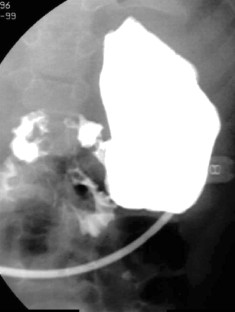

Herman, T., Siegel, M. Feingold Syndrome: Microcephaly, Esophageal Atresia, Type III Laryngeal Cleft, Malrotation, Limb Anomalies. J Perinatol 24, 568–570 (2004). https://doi.org/10.1038/sj.jp.7211144